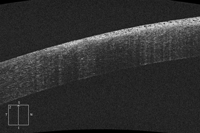

Se obtuvieron imágenes de tomografía de coherencia óptica (OCT) utilizando el protocolo del segmento anterior en el instrumento Zeiss Cirrus (Carl Zeiss Meditec, Jena, Alemania). Las imágenes (Figura 2) muestran hiperreflectividad de todo el espesor del epitelio en la zona afectada y múltiples espacios pequeños, redondos, hiporeflectivos y densamente apretados. Una demarcación abrupta entre la zona afectada y del epitelio sano es evidente, además de una clara separación de la capa de Bowman.

Figura 2. Imagen de OCT de epitelio corneal que muestra un patrón microquístico sobre un fondo hiperreflectivo, superficie lisa, la falta de afectación de la capa de Bowman y demarcación abrupta con el epitelio sano.